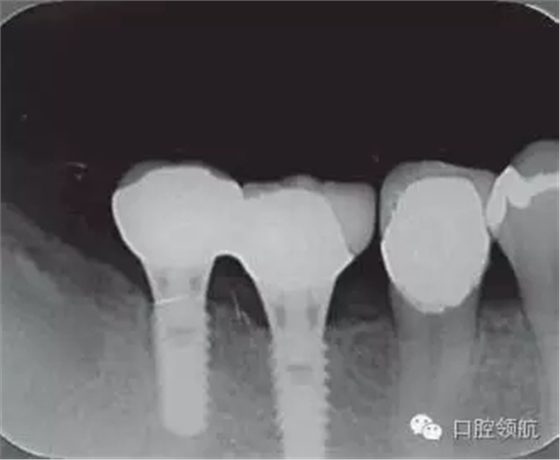

修復體安裝后的2003年1月復診時的X線片上,沒有發(fā)現(xiàn)種植體頸部有骨吸收現(xiàn)象,情況良好(圖2)。但是,2003年8月,因混合陶瓷樹脂部分修復體的破損而進行再制作時,發(fā)現(xiàn)有輕度的咬合疼痛以及舌側(cè)頸部的牙齦有輕壓痛??趦?nèi)沒有觀察到該部位的牙齦紅腫。X線片可以觀察到(左下第6顆牙) 的種植體頸部有達到第4螺紋的骨吸收現(xiàn)象(圖3)。

圖2 沒有發(fā)現(xiàn)種植體頸部的骨吸收(2003年1月)

圖3(左下第6顆牙)的種植體的骨吸收達到第4螺紋(2003年8月)